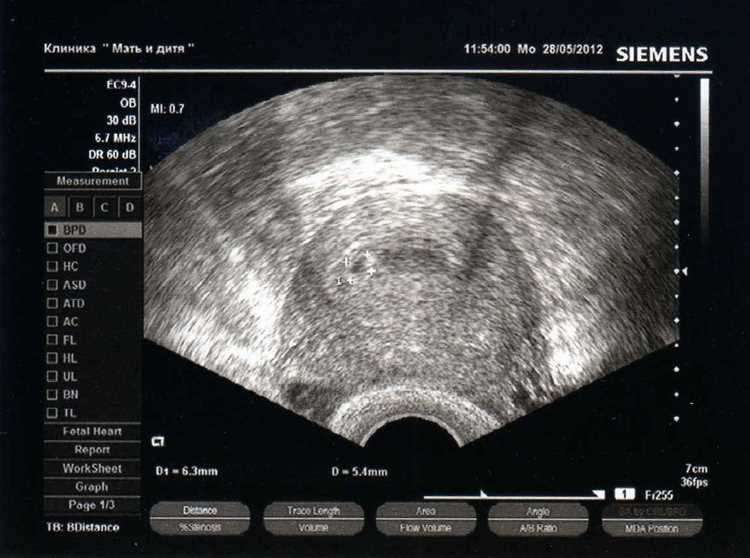

Первое исследование с помощью ультразвука чаще всего проводят на 6-8 неделе гестации. В этот период можно определить наличие??, а также оценить его состояние и место расположения. Данный срок позволяет получить ясное представление о том, многие ли эмбрионы развиваются, что особенно важно при многоплодной ситуации.

Также на 8-10 неделе можно установить сердечную активность эмбриона, что придаёт уверенности в положительном исходе. В этом промежутке времени визуализация становится более чёткой и информативной. Специалисты рекомендуют не затягивать с визитом к врачу, если имеются любые подозрительные симптомы, такие как боли или кровянистые выделения.

Если беременность развивается в норме, последующие проверки в виде ультразвуковых исследований назначают на 11-14 неделе. Это позволяет более подробно изучить анатомию плода, сохранить контроль за его развитием и выявить некоторые возможные отклонения.

Сердцебиение эмбриона можно определить примерно на 6-7 неделе гестации. В этот период размеры эмбриона достигают около 4-5 мм, что позволяет распознать биение сердца. На этом этапе оно может быть заметно не на всех аппаратах. Наиболее точные показатели можно получить при использовании современного оборудования.

На 6 неделе пульсация в сердце становится постоянно заметной, и её частота варьируется от 100 до 180 ударов в минуту. При этом, в зависимости от специфики индивидуального развития, существует возможность зафиксировать первые признаки сердцебиения чуть позже – на 8 неделе.

Для оптимального результата специалисты рекомендуют проводить первый осмотр на ультразвуковом сканировании в 7 недель, когда вероятность обнаружения пульсации значительно возрастает. Важно учесть, что некоторые факторы, такие как положение эмбриона или качество аппарата, могут повлиять на видимость сердечного ритма.

Учитывая потенциальные колебания в развитии, не стоит паниковать, если сердцебиение не удалось зафиксировать на ранних этапах. В таких случаях может потребоваться повторный осмотр через несколько дней для дополнительной оценки состояния.